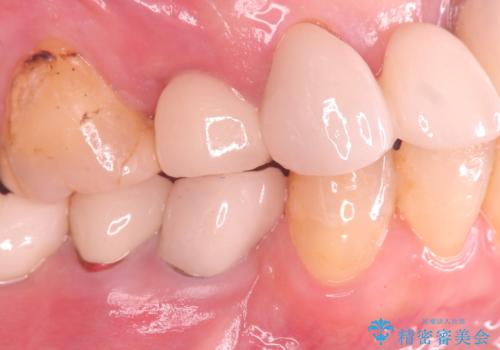

歯の破折 食べる喜びが蘇るインプラント治療